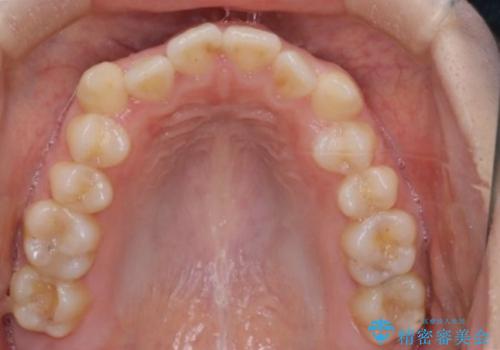

前歯のガタツキ、前歯の噛み合わせ(開咬)をインビザライン治療で治しました

- 前歯のがたつき、噛み合わせが気になるとのことで来院された患者様です。

インビザラインを使用して治療しました。

前歯がしっかり噛んでない状態(開咬)を治すために、前歯にゴムをかける必要があります。ゴムかけは患者様にご協力していただきます。